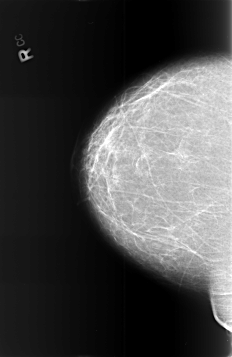

B_3372_1.RIGHT_CC

RIGHT_CC LINES 5712 PIXELS_PER_LINE 3704 BITS_PER_PIXEL 12 RESOLUTION 50 NON_OVERLAY